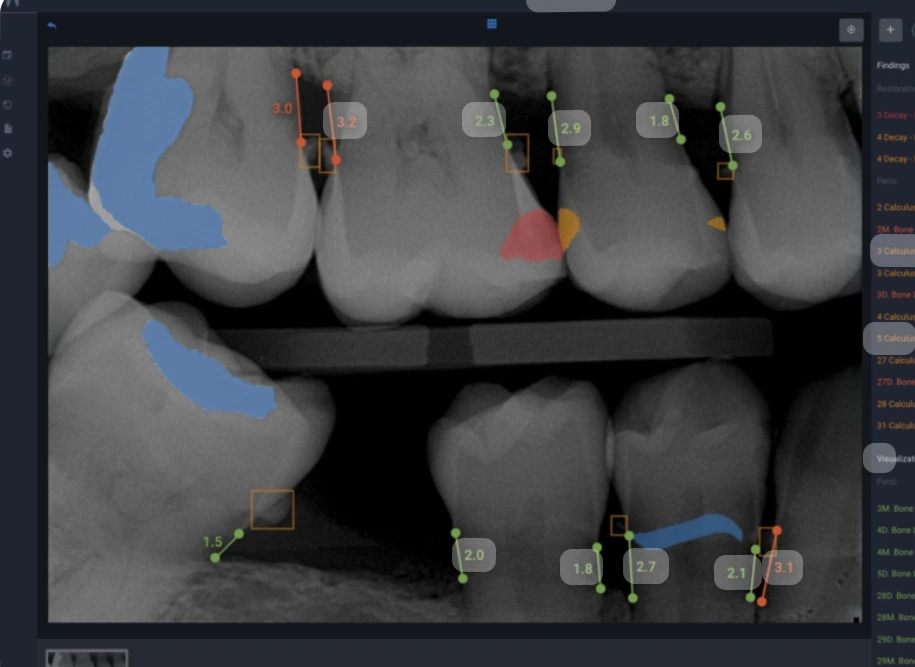

지금 아들놈이 다니는 치과대학원에서는 학생들이 환자를 직접 대하기 전에 simulator로 치료를 하는 과정을 거친다고 한다. 마치 파일럿이 비행기 작동 연습을 미리 해보듯이 비슷한 세팅으로 훈련을 거친 다음 직접 환자를 치료 한다고 한다. 물론 아직도 마네킹을 두고 연습을 하지만, 이미 그 세대에게는 이런 훈련이 어색하지가 않다고 한다. 우리 오피스에서는 Dentrix Ascend 라는 프로그램을 사용하고 있는데, 요즘 Dentrix Ascend 를 열면 제일 먼저 떠는 화면에 A.I. 와 연동되는 업그레이드된 버전을 소개하고 있다. 대충의 내용을 살펴보면 엑스레이만으로 충치의 크기와 위치, Perio condition, Probing depth를 정확히 분석해서 순식간에 차트를 생성해 내고, 그에 따른 치료방법과 후유증까지 정리해 낸다. Two dimensional image 로 그런 것들을 어떻게 정확하다고 말할수 있을까 살짝 무시해 보려다가, Cone beam CT 로 분석을 한다면 어쩌면 더 정확하지 않을까 살짝 우울해 지기도 한다.실제로 오피스들이 업그레이드 버젼을 사용하기 시작했다. 모든 진단과 치료방법을 A.I.가 담당하고 우리는 A.I.가 추천하는 대로 하는, 혹은 A.I.의 진단이 틀렸다고 화내는 우리의 모습이 그려진다. 지금은 이렇게 상상해 볼 수 있는 수준의 기술발전이 예상되지만, 이 단계를 넘게되면 어떤 시대가 올지 궁금하기도 하고, 두려워지기도 한다.